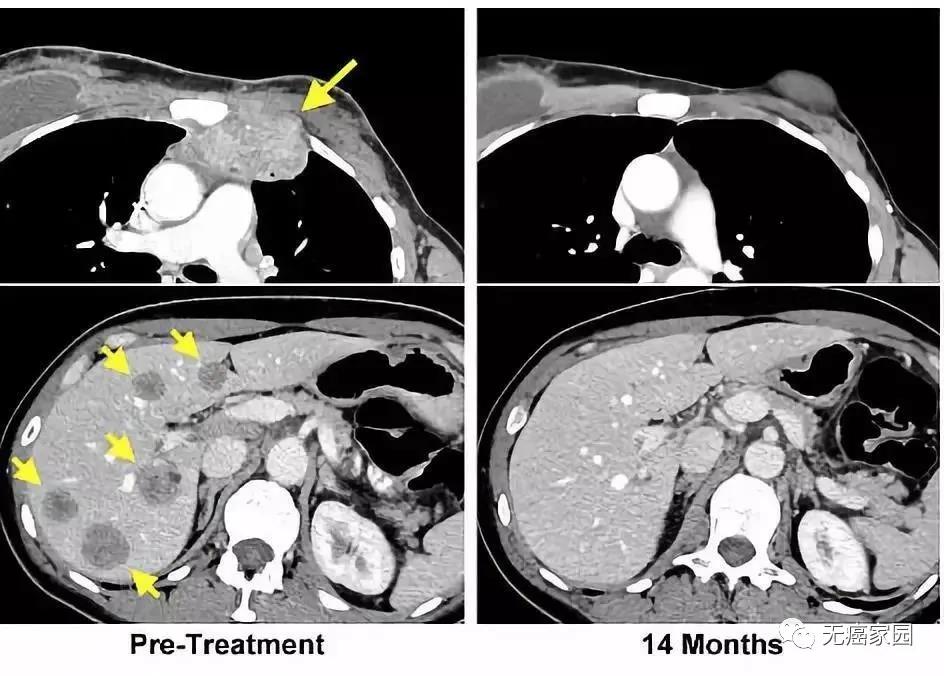

左图黄色箭头是治疗前肿瘤位置;右图是治疗结束14个月后的复查:肿瘤完全消失